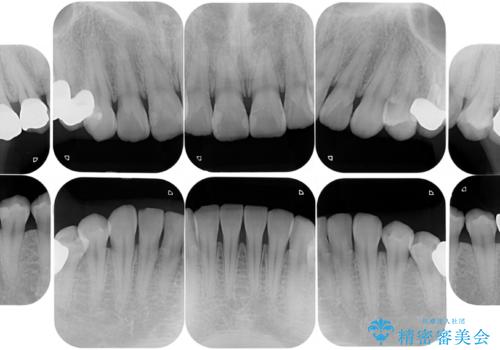

元々噛む力が強く、日常的に歯ぎしりもされるとの事で、セラミックが欠けてしまっていました。歯が割れてしまうリスクを軽減させるため、歯全体を覆うクラウンをメインに補綴治療を行いました。

右上の小臼歯部においては、元々はセラミックインレーでの治療をご提案していましたが、歯や被せ物がまた割れてしまうのが嫌との事で、患者様よりクラウンにしてほしいとの強いご希望がありました。元々の欠損部の面積に対して歯を全周削ることになるため、オーバートリートメントになってしまう事を十分ご説明し、ご納得頂いた上でクラウンによる補綴処置を行いました。

被せ物の色は患者様のご希望により明るめの色(A1)にて作製しております。